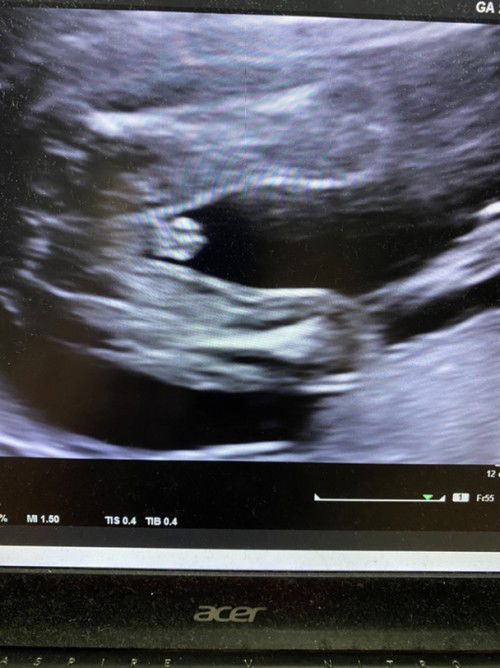

aku buat detail scan swasta gak☺️kangkang cantik ja..takda fikir nak tgok jantina dia🤭sekali scan baby redha tunjuk punai dia😆helok ja punai berdiri..hahaha 22week masa buat detail scan?takda ragu² da..memng baby boy

rasa gegirl ni..sy scan mula2 pn mcm ni..rupa2nya tali pusat dia yg atas tu🤭..scan pusing p pusing mai br nmpk burger..n kali ke 2 scan pn sama burger

sy pula tak nmpk bijinya...yg sy nmpk mcm miss V nya sja...jangan2 yg mcm pistol tu sebenarnya tali pusat dia🤔

doc ade bgthu,kalau telur,lain bentuk dgn burger sign utk girl. ni pon sbb xnmpk pistol

mcm boy. sbb ada buah tu. kalau girl,burger sign. xterkeluar mcm tu🤭